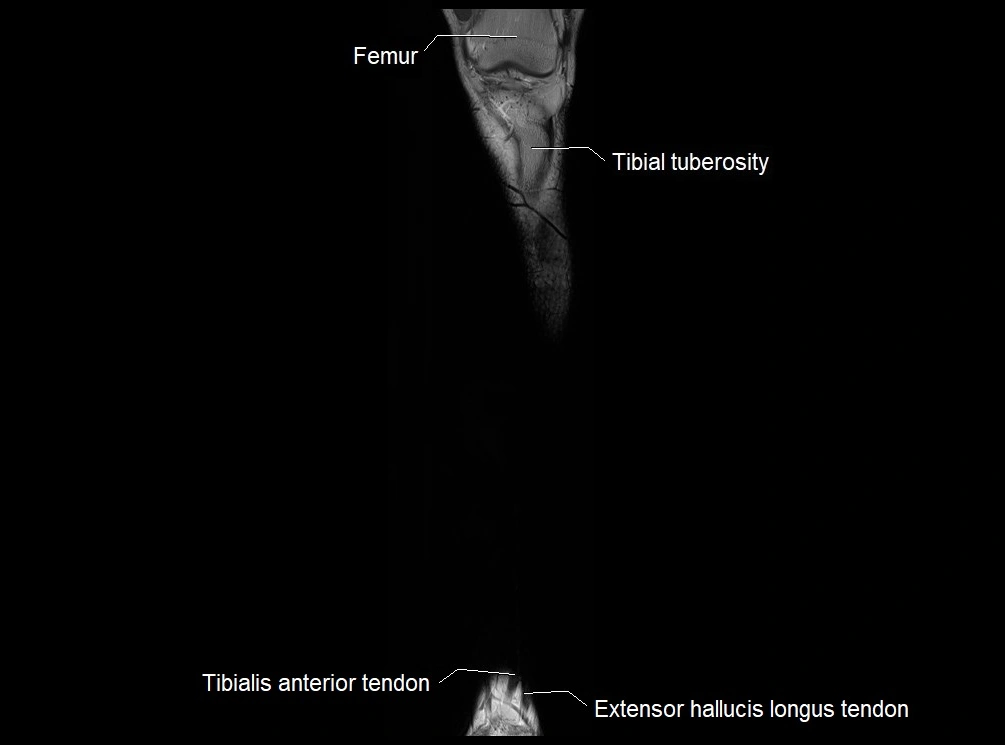

MRI image